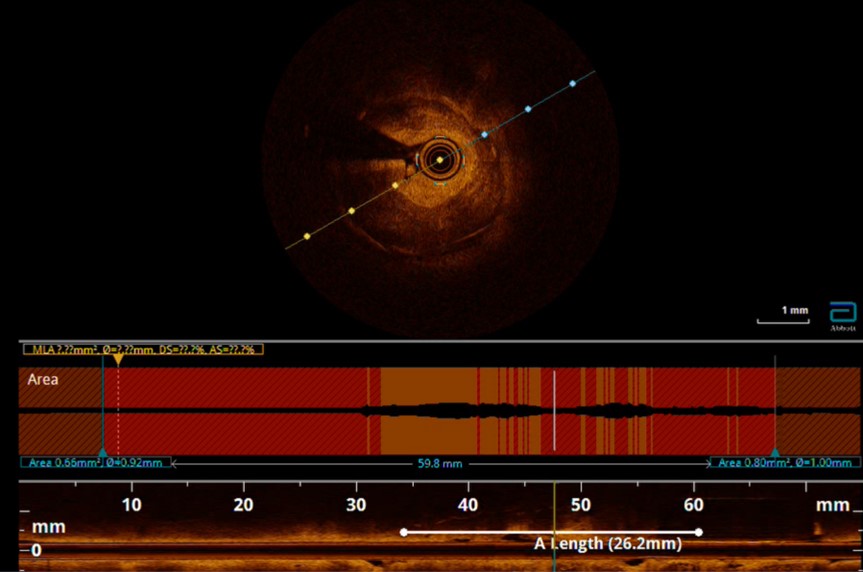

Contralateral injection approach PCI. Difficulty in wiring occluded LAD segment with Fielder XT-A and Gaia Next 2nd despite with Corsair Pro XS support. Wiring of LAD was successful after escalation to Gaia Next 3rd. After failed attempts to deliver microcatheter, 0.9mm excimer coronary laser atherectomy (ELCA) was performed for 12 cycles (60/80, blood medium) followed by predilatation with Sapphire 3 0.85/10 and Sapphire 1.5/10. Delivery of the microcatheter over the lesion was then successful. Gaia Next 3rd wire then exchanged to NS Runthrough. Predilatation of the lesion with NC Sapphire 2.0/15 and NC Trek 2.5/15, however noted balloon severe underexpansion. Optical Coherent Tomography (OCT) performed with Dragonfly Opstar showed severely calcified neoatherosclerosis. Four runs of 1.5mm burr rotational atherectomy was then performed at 180,000rpm, followed by another three runs of 1.75mm burr rotablation at 180,000rpm. We then deployed DES Xcience Skypoint 2.5/38 to m-dLAD and another DES 3.5/28 Xcience Skypoint to the LM-pLAD region due to dissection flap evident in OCT. Lesion segment between DES was subsequently prepared with intravascular lithotripsy (IVL) 3.0/12 for 80 shocks and NC Pantera Leo 3.0/15 before deploying Xcience Skypoint 3.0/15. DES optimization was then performed under OCT guidance. Finally, DCB 3.0/20 Sequent Please Neo DCB was deployed to mLAD ISR for 60 seconds. Staged PCI to RCA was performed with IVL followed by DES deployment under imaging guidance.

Case Summary